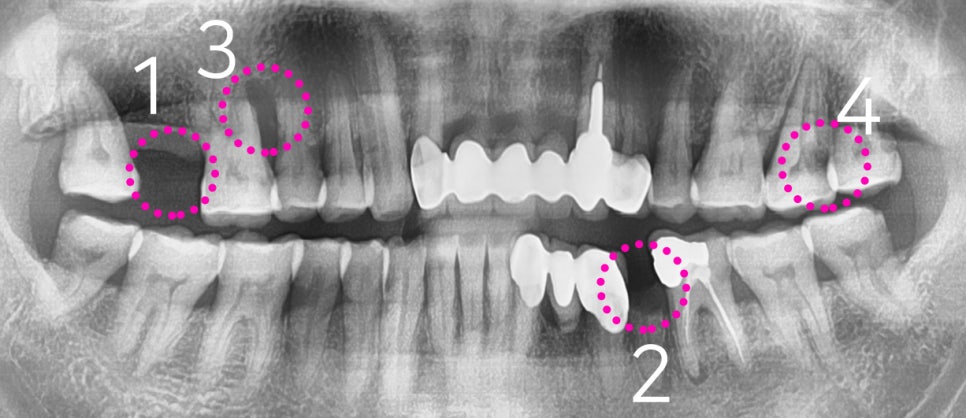

1) #17번 치아 결손

2) 소구치 잔존 치근만 남아있기에 발치 결정

3) apex lesion (뿌리 염증) 에 따라 발치 결정

4) proximal caries (사이충치)에 따라 신경치료

이렇게 4가지의 특이소견이 관찰 되었었습니다.